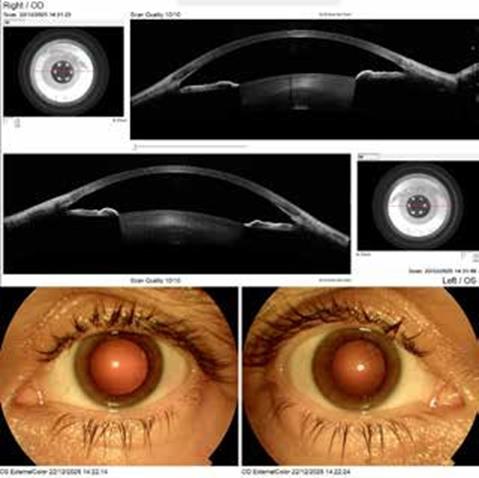

Η OCT (Swept Source ή και Spectral Domain) τεχνολογία μπορεί να απεικονίσει την ανατομική μεταβολή της πυκνότητος του κρυσταλλοειδούς φακού, ακόμη και αν αυτή δεν είναι ορατή κατά τη βιομικροσκόπηση. Στην Εικόνα 1 είναι ορατή μια αρχόμενη πύκνωση στον πρόσθιο φλοιό (ενώ ο πυρήνας είναι διαυγής) ενός ασθενούς ηλικίας 49 ετών, με οπτική οξύτητα 1.0 (decimal scale, Snellen chart) άμφω, χωρίς κλινικά στοιχεία καταρράκτη κατά τη βιομικροσκόπηση, αλλά με υποκειμενική ελάττωση της ποιότητας της όρασης κατά το τελευταίο έτος. Επίσης, η Scheimpflug τεχνολογία μπορεί να εφαρμόσει πυκνομέτρηση (densitometry) για τον ίδιο σκοπό. Και οι δύο τεχνολογίες είναι χρήσιμες στην αντικειμενική καταγραφή των μεταβολών του φακού και την αξιολόγηση του ΣΔΦ ακόμη και πριν την κλινική εμφάνιση καταρράκτη.1 Όμως, δεν προσφέρουν αντικειμενική ποσοτικοποίηση και αξιολόγηση της λειτουργικότητος του κρυσταλλοειδούς φακού και δεν μπορούν να συσχετίσουν τη λειτουργικότητα του φακού με το μέγεθος της κόρης. Η τεχνολογία, η οποία παρέχει αντικειμενική αξιολόγηση της λειτουργικότητος του φακού (σε συνάρτηση με τη διάμετρο της κόρης), είναι η Αμπερομετρία.3,4